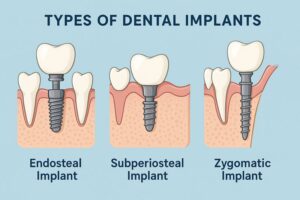

סוגי השתלות שיניים וסוגי שתלים דנטליים

שתלים בזאליים – כשאין מספיק עצם